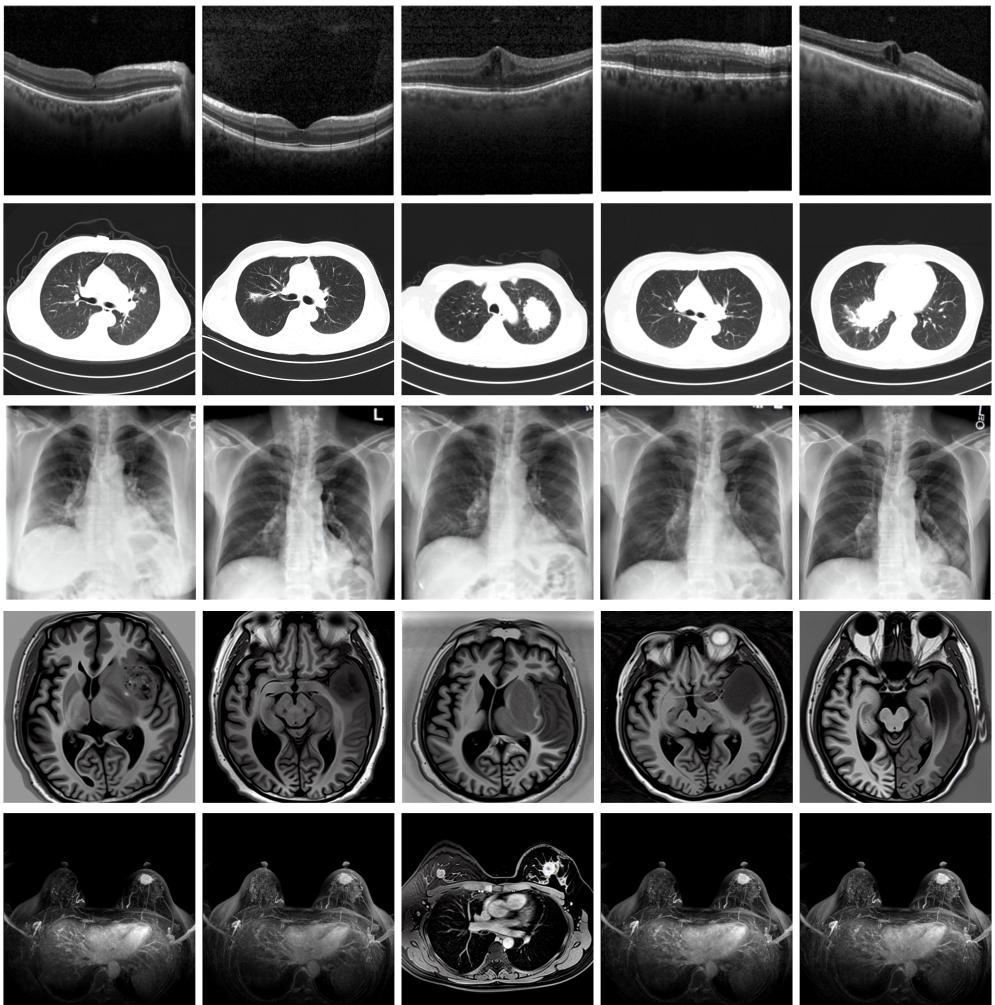

记者从北京大学未来技术学院获悉,北京大学与温州医科大学的研究团队建立一种生成式多模态跨器官医学影像基础模型(MINIM),可基于文本指令以及多器官的多种成像方式,合成海量的高质量医学影像数据,为医学影像大模型的训练、精准医疗及个性化诊疗等提供有力技术支持。该成果已于近期在国际权威期刊《自然·医学》上在线发表。图为由MINIM生成的高质量医学合成图像(受访者供图)

“目前公开的医学影像数据非常有限,我们建立的生成式模型有望解决训练数据不够的问题。”北京大学未来技术学院助理研究员王劲卓说,研究团队利用多种器官在CT、X光、磁共振等不同成像方式下的高质量影像文本配对数据进行训练,最终生成海量的医学合成影像,其在图像特征、细节呈现等多方面都与真实医学图像高度一致。

实验结果显示,MINIM生成的合成数据在医生主观评测指标和多项客观检验标准方面达国际领先水平,在临床应用中具有重要参考价值。在真实数据基础上,使用20倍合成数据在眼科、胸科、脑科和乳腺科的多个医学任务准确率平均可提升12%至17%。